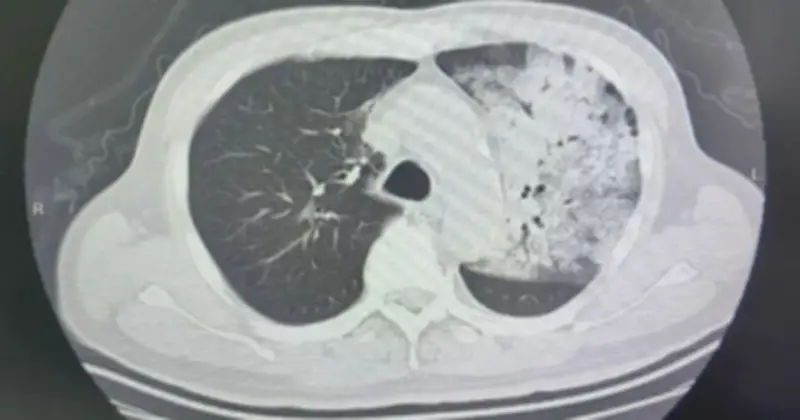

Sau khoảng một tuần điều trị tại bệnh viện địa phương, tình trạng bệnh nhân đột ngột xấu đi với khó thở và rối loạn ý thức. Kết quả chụp CT cho thấy hai phổi bị nhiễm trùng nặng, gần như "trắng xóa". Dù đã được hỗ trợ thở máy, tình trạng oxy máu vẫn không cải thiện, buộc các bác sĩ phải can thiệp bằng ECMO để tạm thời ổn định dấu hiệu sinh tồn.